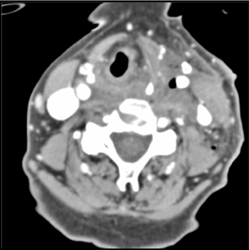

Prominent Right Jugular Vein